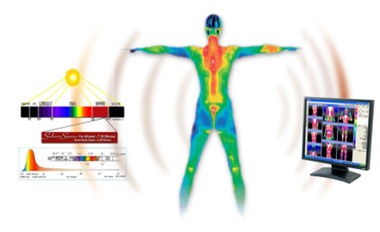

红外热成像主要采用世界先进的非致冷焦平面红外探测技术,接收人体辐射出的红外线,通过计算机处理以热图的形式客观地记录人体的热场,经专用软件加以分析比较,反映机体的功能状况。

二、原理:人体无时不刻地对外发射红外辐射能。研究证明,红外辐射与人体的血液循环、组织代谢、神经的功能状态和组织结构密切相关。正常的人体功能状态有正常的色彩图,异常的功能状态有异常的色彩图。比较和分析正常和异常色彩图的差异和规律,就可用于诊断,推论机体的生理,病理状态。结合临床,可指导和辅助临床的诊断和治疗。